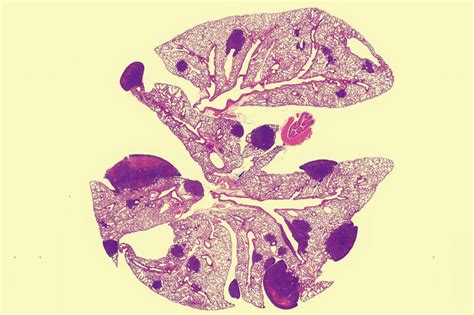

Syndróm polycystických vaječníkov (PCOS)

Syndróm polycystických vaječníkov môže viacerými spôsobmi ovplyvniť plodnosť žien. V dôsledku nadprodukcie hormónu androgén sa môže zastaviť dozrievanie vajíčok, na vaječníkoch sa vytvorí akási hrubá kôra, ktorá zabraňuje vypudeniu vajíčok a okolo prasknutých folikulov sa môžu vytvoriť tekutinou naplnené cysty až do veľkosti 8 mm. Liečba PCOS dnes už nie je nemožná, pri prvých príznakoch sa odporúča obrátiť na lekára: bolesť podbruška, kŕče, nepravidelná menštruácia, zvýšené ochlpenie, aknózna pleť, rapídne chudnutie alebo priberanie na váhe, inzulínová rezistencia, vypadávanie vlasov.